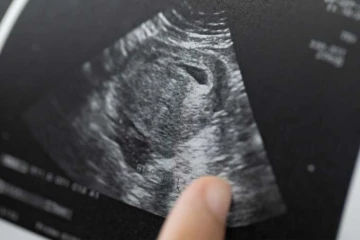

SB1236 would have banned abortion from the detection of a fetal heartbeat, usually around six weeks of pregnancy. It was opposed by the state's bishops, and Tennessee Right to Life, over concerns it would not stand up to judicial scrutiny.

Sen. Mark Pody, its sponsor, has amended SB1236 effectively to declare viability as beginning from conception: "A pregnancy is presumed to exist and to be viable upon finding the presence of human chorionic gonadotropin (HCG) using a test that is consistent with standard medical practice." Some court rulings, such as Planned Parenthood v. Casey, have linked governments' ability to regulate abortion with the viability of the child.